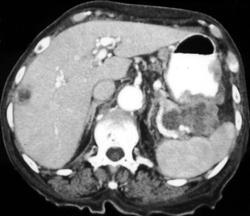

GIST Tumor